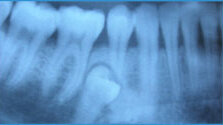

Бывают ли у взрослых молочные зубы?

Наличие у взрослых молочных зубов нельзя отнести к области фантастики или юмора. Такое явление иногда можно встретить в стоматологической практике. Что же способствует тому, что молочный зуб может сохраниться...